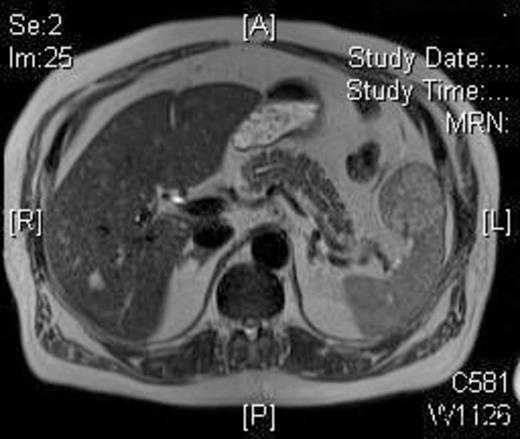

A 58-year-old Caucasian man presented with chest pain, on a background of type-II diabetes mellitus, hypertension and hypercholesterolaemia. A Cardiologist excluded ischaemic heart disease. Full blood count was normal, and an ultrasound scan of the abdomen revealed a 5.5-cm splenic lesion. Computed tomography (CT) revealed a 55mm X 36mm hypodense lesion in the upper pole of the spleen, while magnetic resonance imaging (MRI) demonstrated a well-circumscribed exophytic round mass arising from the anterior aspect of the spleen with features compatible with a benign solid tumour of uncertain malignant potential and multiple liver haemangiomas [Figures 1 and 2]. We proceeded to LPS after the patient had received preoperative vaccinations lest total splenectomy might be necessary.

T1W post-gadolinium MRI: the mass demonstrates a degree of late enhancement